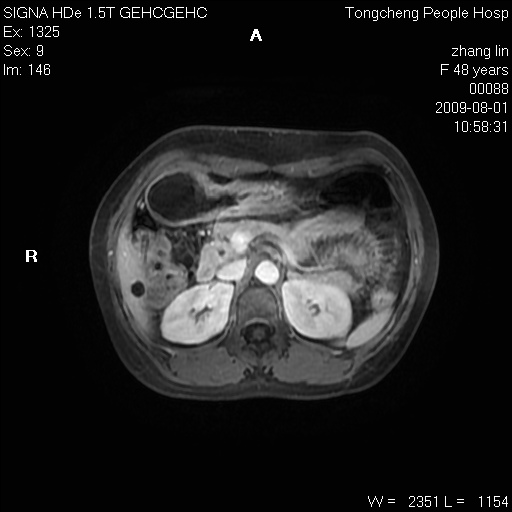

女,48岁。健康体检,彩超发现右肾占位性病变。平素健康。

临床诊断:右肾占位性病变,性质待定(囊肿?肿瘤?)。

上中腹部mr平扫+增强扫描,图像如下:

右肾上极见一类圆形病灶,t1wi呈等信号t2wi呈等高混杂信号,三期增强无强化,边界清---考虑囊肿出血。

同反相位均表现为等信号,病变无强化,考虑含蛋白的囊肿可能,弥散加权相或许有些帮助,